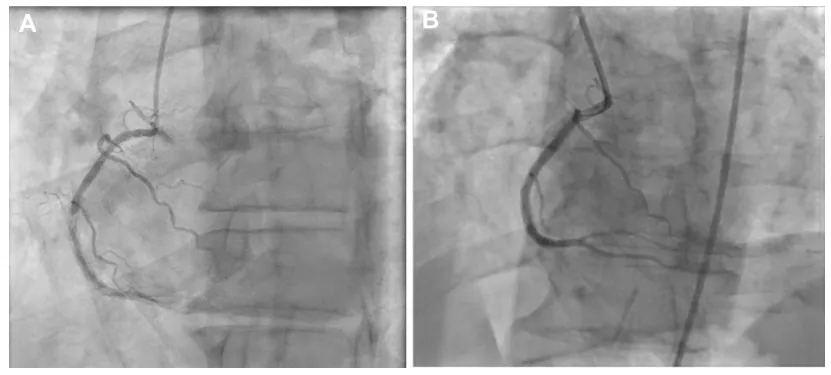

采用L-OPN技术获得了极好的冠脉造影与血管内成像结果(图4)。

图4:(A)术前冠脉造影显示血管中段重度狭窄(≥90%)伴远段重度狭窄(≥80%),导致TIMI血流分级2级。(B)ELCA+OPN球囊处理后血管造影显示管腔改善,血管轮廓恢复平滑。